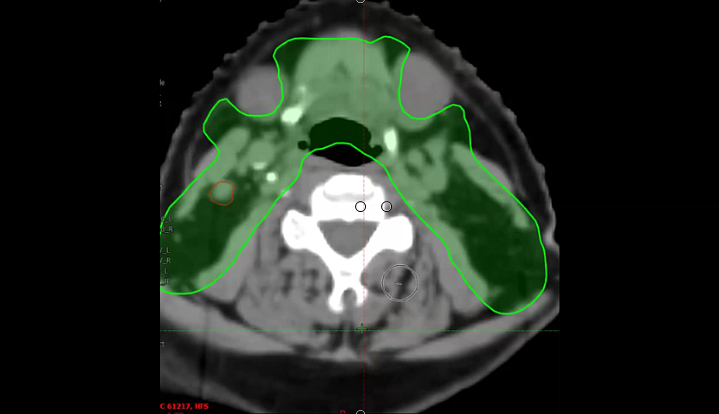

nasopharynx, MRI, PET, CT, NPX carcinoma, balloon procedure, right nasal pharyngeal carcinoma, 2A node, microscopic disease, T1, CLL, right parotid mass, squamous cell, right superficial parotidectomy, modified neck dissection, right temporal skin lesion excision, lymph node, ECE, bolus, dissecte...